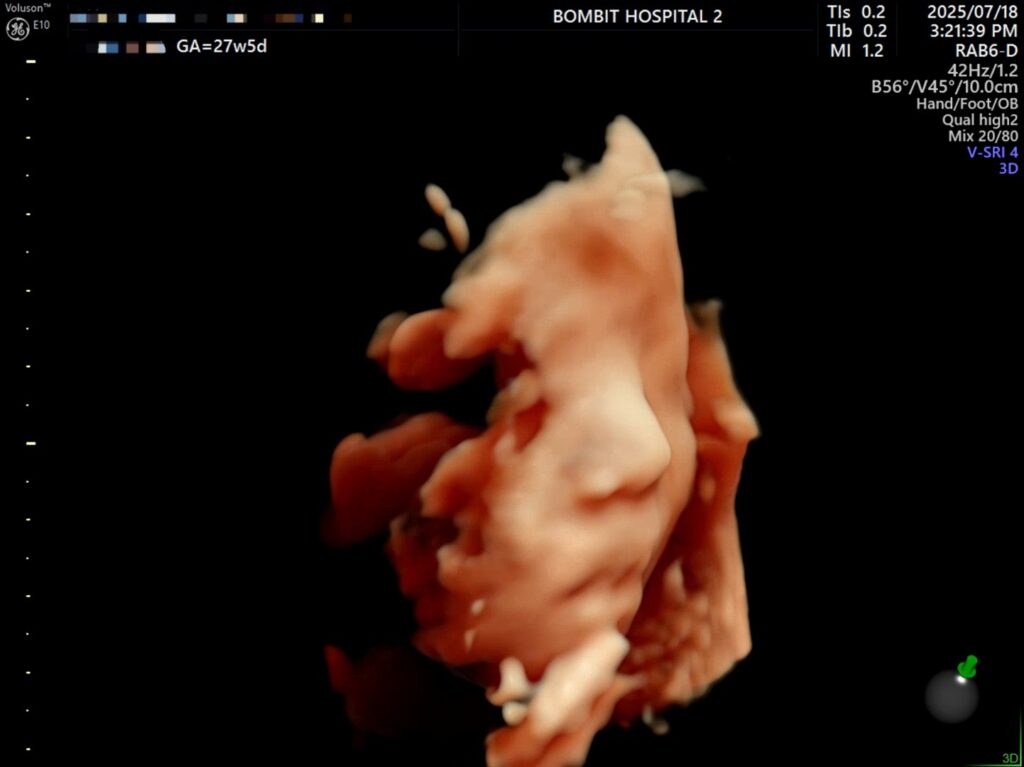

– 처음에 보여준 귀.. 귀욥

– 통통한 손가락